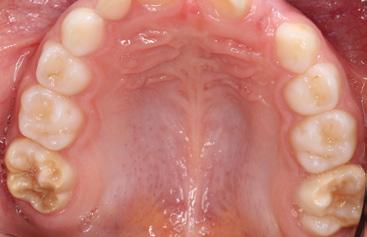

Der Begriff der «Molaren-Inzisiven-Hypo mineralisation», abgekürzt MIH, existiert seit 2001 [1]. Beschrieben wird eine syste misch bedingte Hypomineralisation des Zahnschmelzes bei einem bis zu vier ers ten bleibenden Molaren. Zudem können die ersten bleibenden Inzisiven betroffen sein, sie müssen es aber nicht (Abb. 1, 2).

Für die Diagnose einer MIH ist der klini sche Befund entscheidend. Kriterien zur Erfassung der hypomineralisierten Zähne liegen von der EAPD vor [14], die wie folgt festgelegt sind: klar umschriebene Opazi täten (Abb. 1, 2), posteruptive Schmelzab brüche (Abb. 1), atypische Restaurationen (Abb. 3) und atypische Extraktionen. Diffe rentialdiagnostisch müssen u. a. folgende Krankheitsbilder in Betracht gezogen wer den: Fluorosen, erbliche Strukturanoma lien (Amelogenesis imperfecta) und exogen bedingte Defekte (Trauma, Turnerzahn, Karies).

Le terme d’«hypominéralisation des mo laires et des incisives», en abrégé MIH, existe depuis 2001 [1]. Il décrit une hypo minéralisation amélaire d’origine systé mique sur une à quatre premières mo laires permanentes. De plus, les premières incisives permanentes peuvent être tou chées, mais pas nécessairement (Fig. 1, 2).

Pour le diagnostic d’une MIH, le résultat clinique est décisif. Des critères de dé tection des dents hypominéralisées sont disponibles auprès de l’EAPD [14] et sont définis comme suit: opacités claire ment circonscrites (fig. 1, 2), cassures postéro-supérieures de l’émail (fig. 1), restaurations atypiques (fig. 3) et extrac tions atypiques. Le diagnostic différen tiel doit prendre en compte, entre autres, les pathologies suivantes: fluoroses, anomalies structurelles héréditaires (amélogénèse imparfaite) et défauts d’origine exogène (traumatisme, dent de Turner, carie).

Fig. 1: MIH sur les dents 16 et 26. La dent 16 présente déjà un effondrement postéroéruptif de l’émail dans la zone distale, la dent 26 présente des opacités délimitées.

Fig. 2: Patiente de la fig. 1. Les deux incisives centrales supérieures présentent chacune une opacité circonscrite.